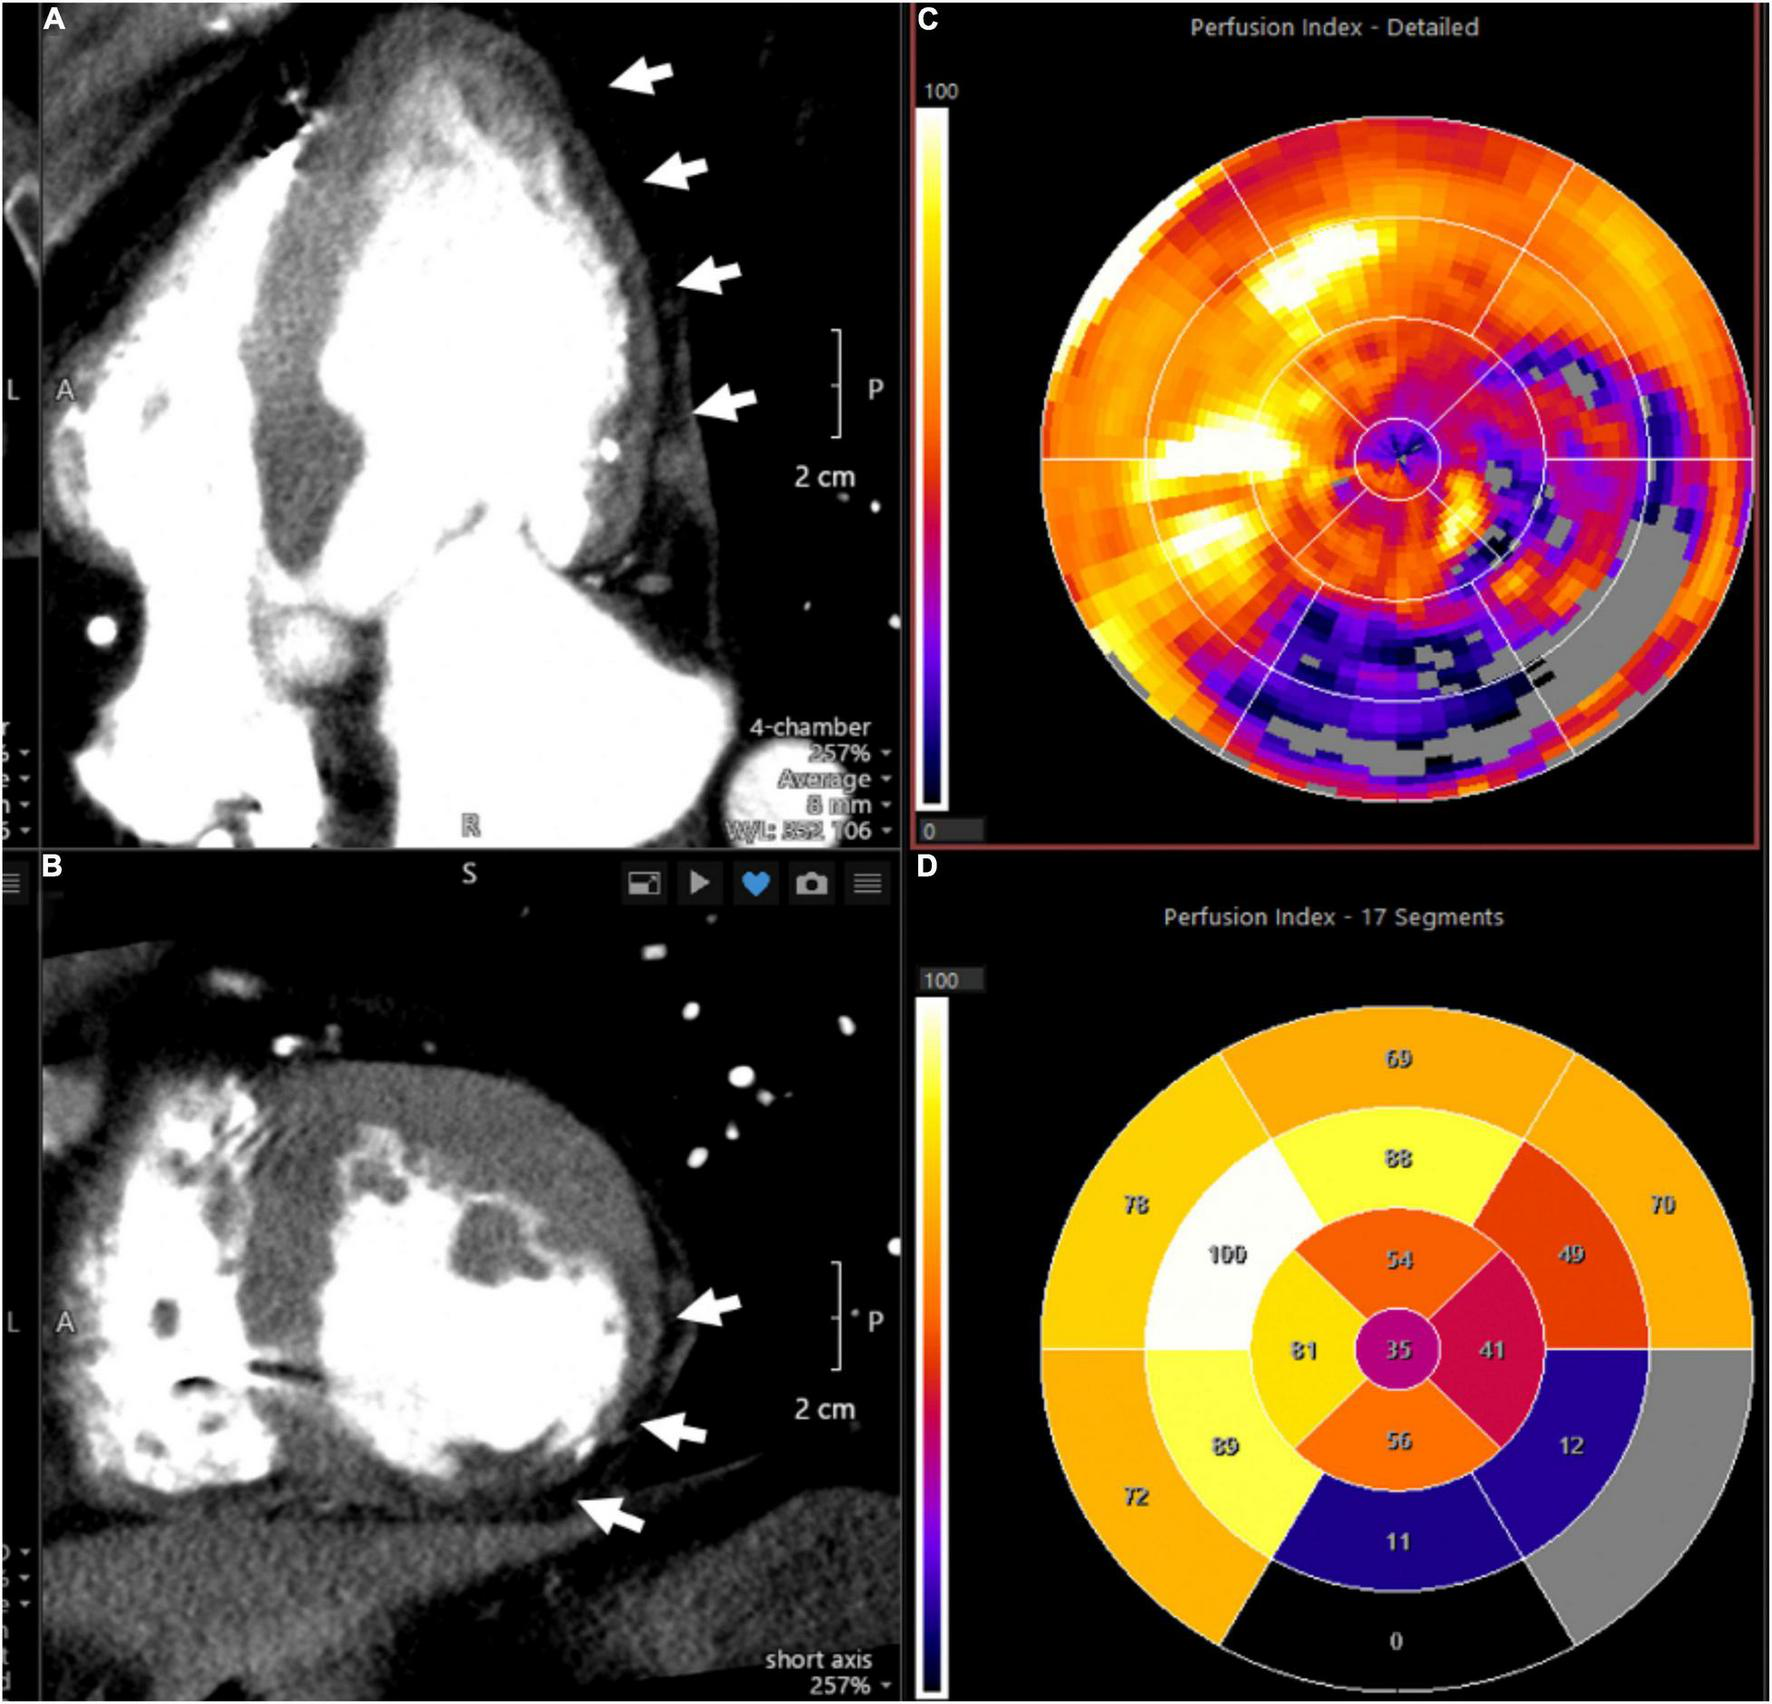

The homogeneity of myocardial perfusion can be readily assessed by its uptake of iodine contrast medium and its associated X-ray attenuation. George et al. demonstrated that myocardial perfusion can be quantified using CT and that reversible perfusion defects can be identified after vasodilator challenge analogous to nuclear imaging techniques (71). CT scanning is performed using injection of an iodinated contrast agent with prospective electrocardiographic gating. Microvascular function may be assessed by determining MBF at rest and after vasodilator challenge with abnormal flow reserve typically defined as a ratio of <2.0 (60). In the absence of obstructive CAD and local myocardial perfusion defects, reduced MFR can be attributed to microvascular dysfunction. Figure 4 shows an imaging example of a patient with a severe myocardial perfusion defect in the lateral and posterolateral walls post infarct.

FIGURE 4

Representative CT perfusion images and polar plots. Images demonstrate severe myocardial perfusion abnormalities in the lateral and posterolateral walls in a patient with history of myocardial infarction. (A) Depicts a cardiac four-chamber view with arrows pointing to hypodense areas in the subendocardial and mid myocardial levels, representing perfusion defects. In addition, thinning of the myocardium is consistent with prior infarct. (B) Provides a cross-sectional assessment of the same case. (C) (Polar plot) shows the corresponding perfusion indices, with the affected myocardial segments provided in (D).